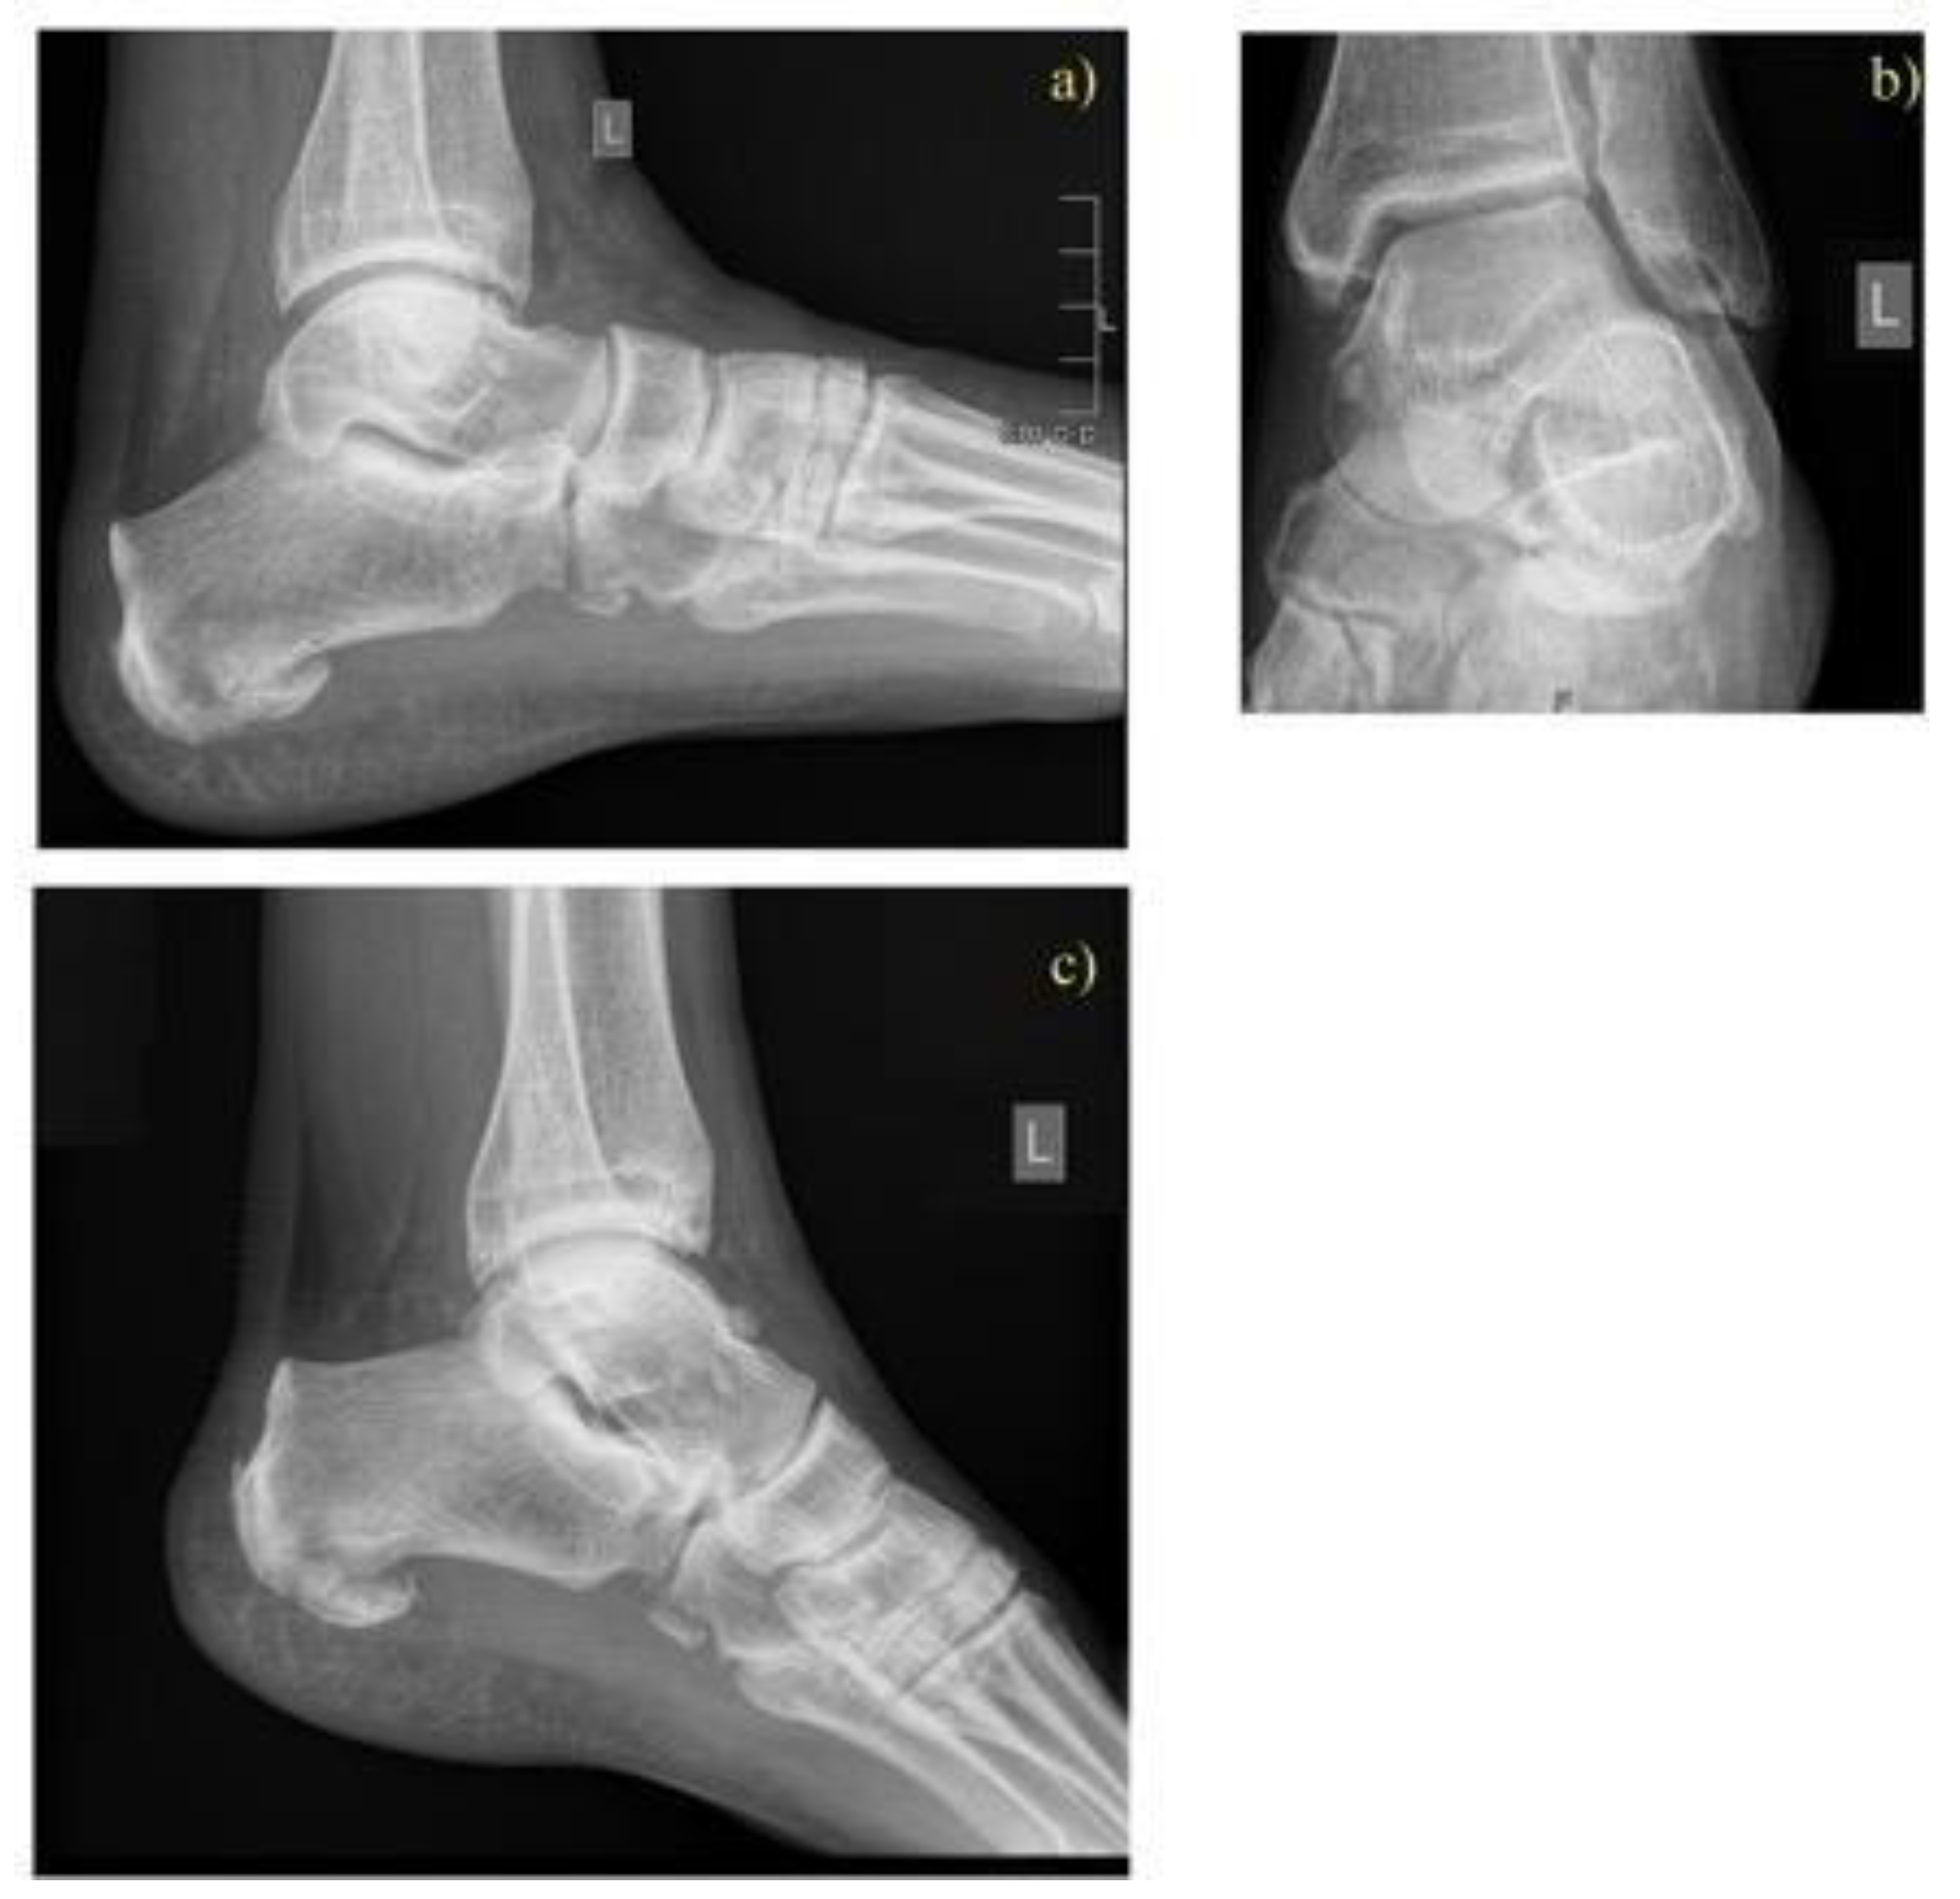

2.2. Treatment Methods